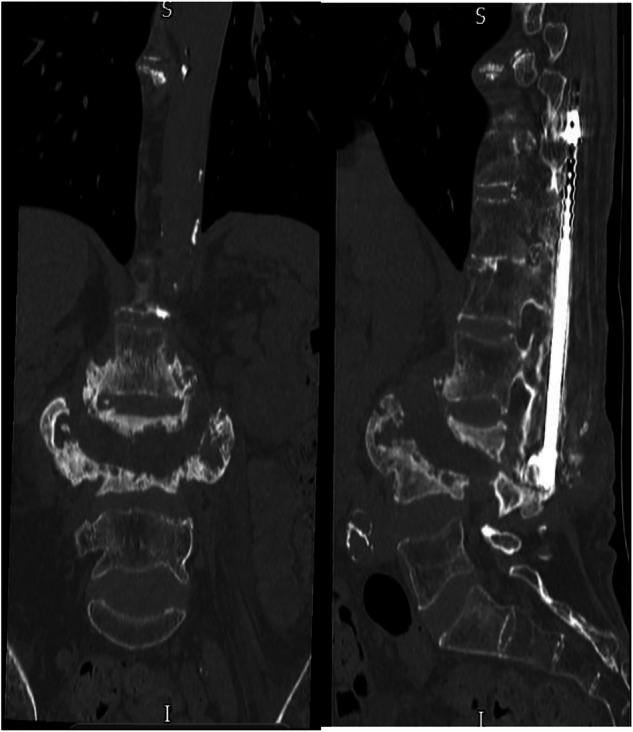

研究设计:回顾性分析6例Charcot脊柱关节病。目的:评价Charcot关节病的病因、临床表现(如疼痛、躯干不稳、自主神经反射障碍、痉挛)、症状发作前潜伏期、脊柱受累区及治疗策略。地点:英国国家脊髓损伤中心。方法:对6例确诊为Charcot型脊柱关节病的患者进行资料收集和分析。检查的变量包括病因、临床表现、受影响的脊柱区域、潜伏期和治疗方法的结果。对保守治疗和手术干预策略进行了评价。结果:患者均表现为疼痛、躯干失去控制、自主神经反射障碍、痉挛等常见临床表现,症状发作前潜伏期不同。胸椎是最常见的受累部位。在大多数病例中,保守治疗成功地稳定了症状,而在严重的躯干不稳定、难治性疼痛或影响活动的畸形的情况下,手术干预是必要的。结论:保守治疗应是沙尔科关节病的首选治疗方法。手术干预保留给有重大临床进展的病例,如未解决的疼痛,躯干畸形导致的活动受限,或脊柱病理引起的紧急并发症。

Results: Patients exhibited common clinical manifestations such as pain, loss of trunk control, autonomic dysreflexia, and spasticity, with varying latency periods before symptom onset. The thoracic spine was the most frequently affected region. Conservative management successfully stabilized symptoms in most cases, while surgical intervention was necessary in instances of severe trunk instability, refractory pain, or deformity impacting mobility.